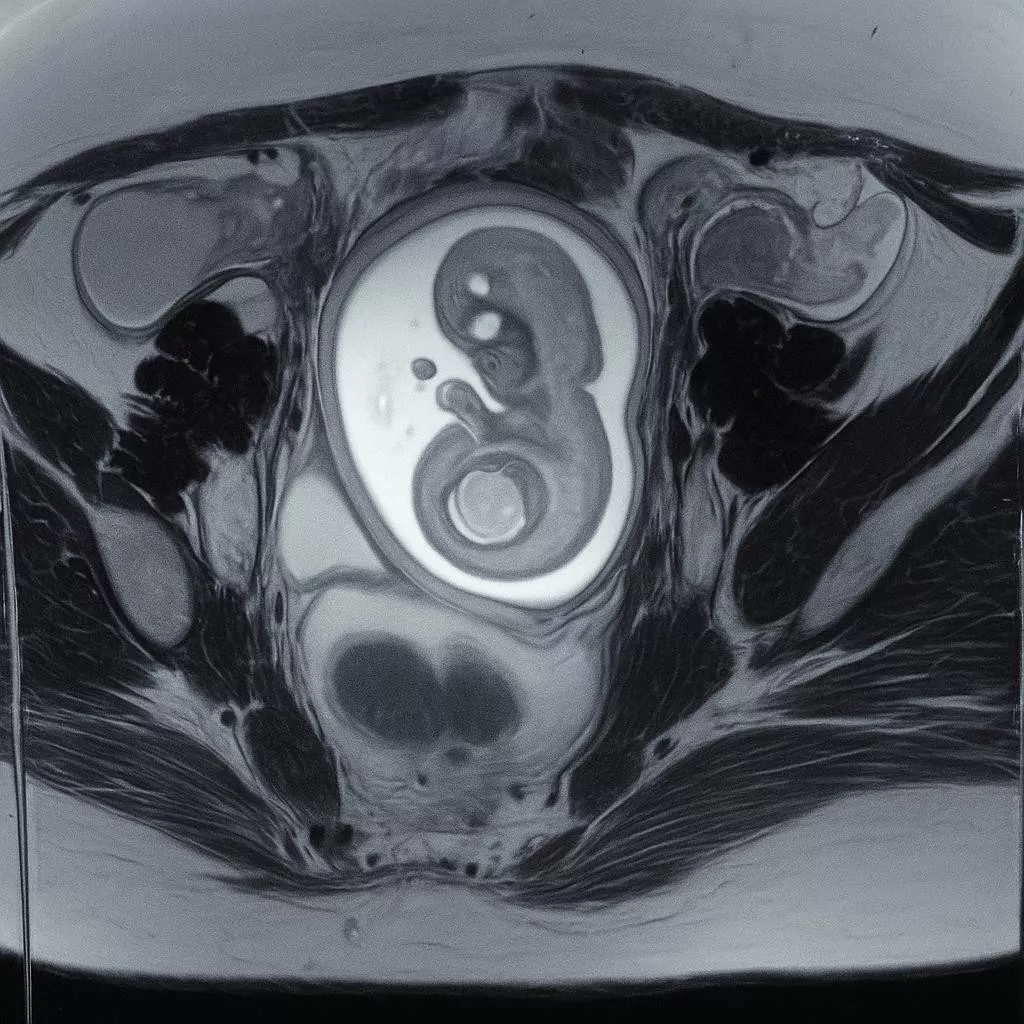

- Ultrasound (13–14 weeks): Live fetus, CRL 80.9 mm, FHR 168 bpm, no anomalies. Bilateral ovarian cysts noted (right ~69×51 mm, left ~32×24 mm) with papillary projections.

- MRI pelvis (12/07/2025): Right adnexal mass 75×55×46 mm, left adnexal mass 30× 25×53 mm, both complex with septations and vascular papillary projections; no extra-ovarian spread.